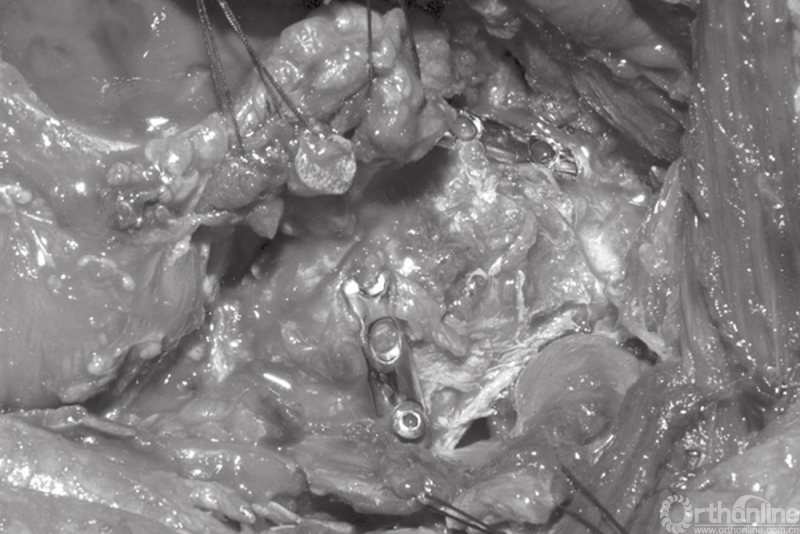

A和B髋臼后壁合并后柱骨折的固定

45岁男性患者,交通事故导致左侧髋臼后柱及后壁骨折。注意骨折线向上延伸以及髋臼顶的骨块。选择后侧入路,以两块钢板固定。同时进行关节囊外大转子截骨并以两枚螺钉固定。